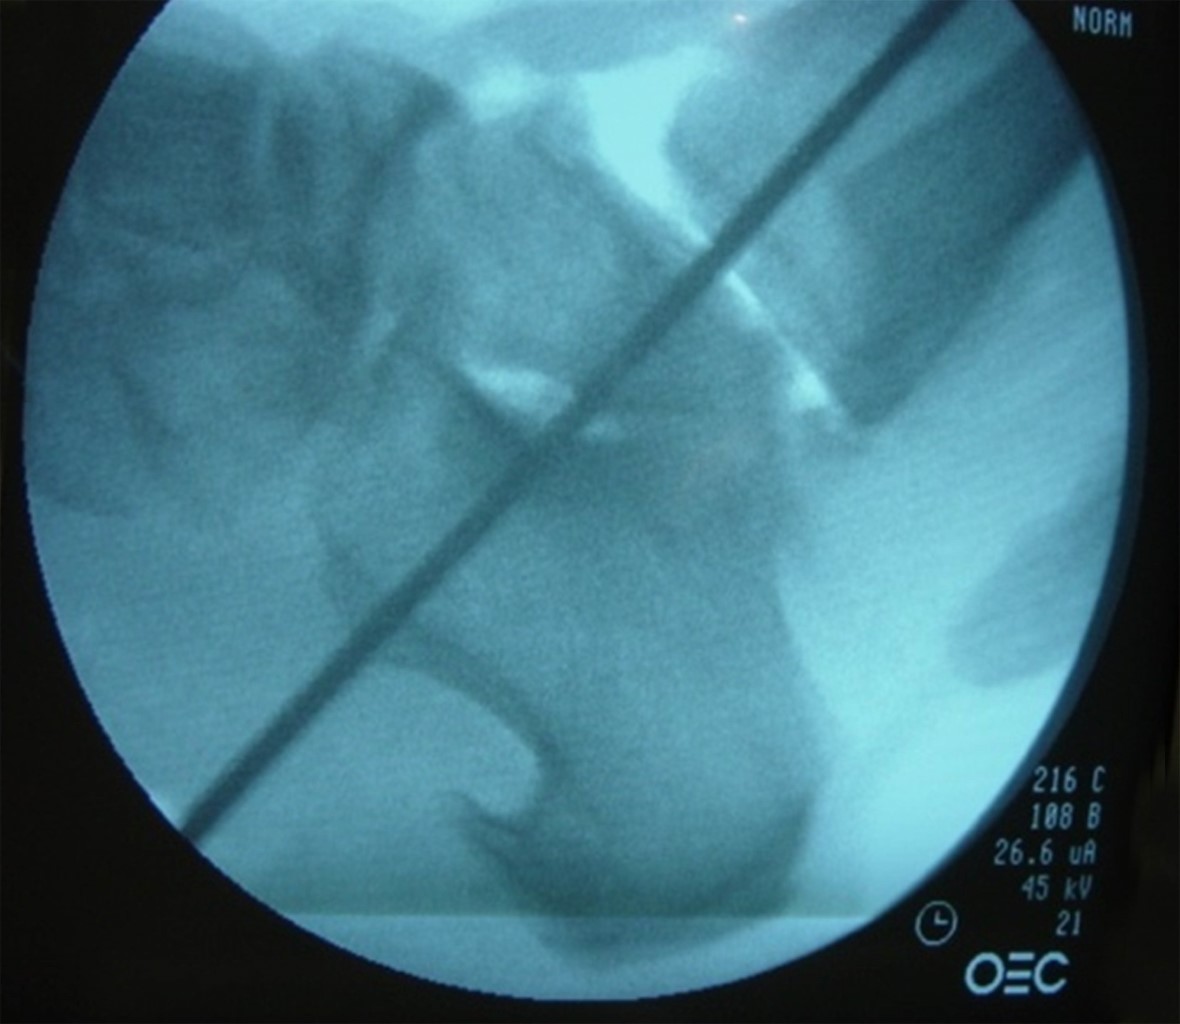

Se continúa con la incisión plantar para el orificio de entrada del clavo retrógrado, introducción del clavo guía, tomando como referencia el eje de la tuberosidad anterior de la tibia y el segundo rayo y se verifica la dirección mediante intensificador de imágenes. Se realiza fresado retrógrado del canal para la introducción del clavo, longitud 140 × 10 mm, (se utilizó el mismo clavo centromedular en todos los pacientes, diseñado en el servicio de deformidades neuromusculares) (Figura 2).

Figura 2